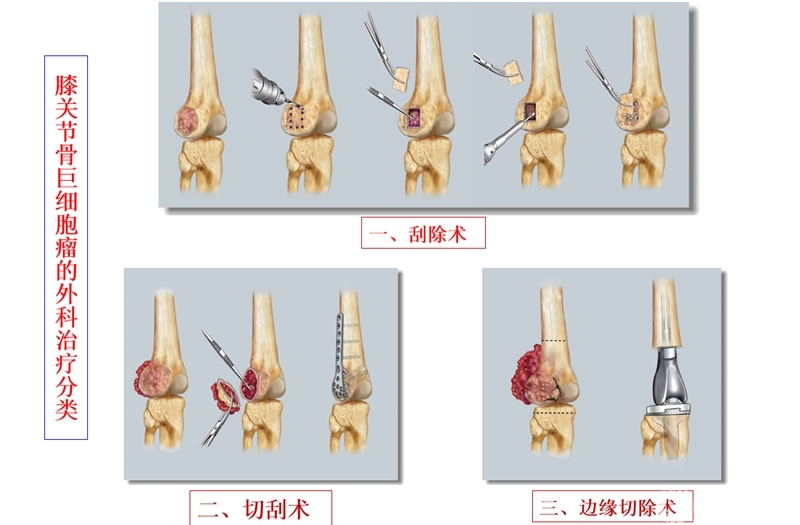

临床上骨巨细胞瘤的外科治疗可根据分类确定手术范围和程度,对于骨强度好一般采取刮除并植骨;骨强度差且连续性完整的,多选用手术刮切结合钢板植入;而出现骨连续性中断的,往往需要切除后行假体植入。

四是在第二章中,除对骨肿瘤的外科治疗进行了详细的阐述外,还对国人好发的骨巨细胞瘤的诊疗进行了详细介绍,同时对四肢骨肿瘤假体的设计特点和应用进行了总结,有助于临床医师更好地掌握假体重建的技术,更好地选择重建假体。